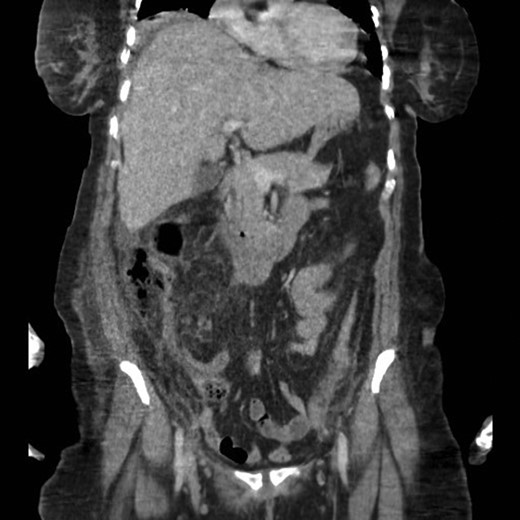

A CT scan revealed an appendix with an enhanced oedematous wall, adjacent retroperitoneal subhepatic air and mild collection indicative of a perforated subhepatic appendix (Fig. 1).

The patient underwent an urgent laparotomy, which revealed pus that was evacuated. The appendix was found to be retrocecal, subhepatic and perforated.